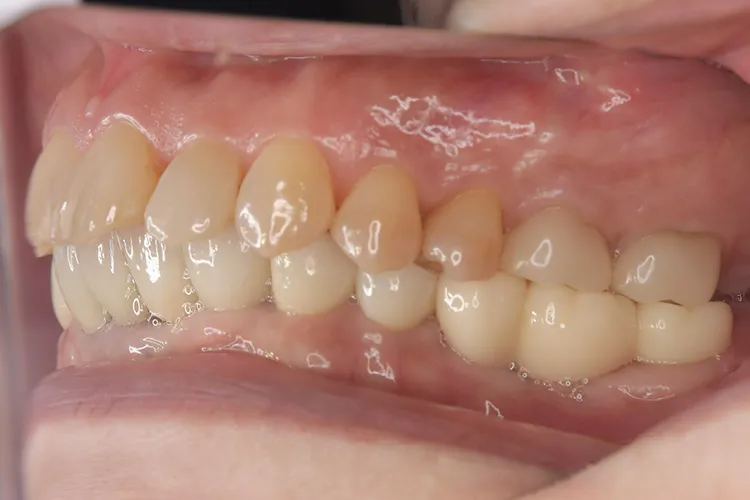

治療前

治療後

症例2/

臼歯1本

- 治療期間

- 3ヶ月

- 費用

- 51万円(税込)

治療内容

第一大臼歯1歯欠損をインプラントで回復したケースです。第一大臼歯は永久歯の中で一番最初に生える歯ですが、一番早く傷んでしまう歯でもあります。噛む力の60%を負担し噛み合わせの安定に大きく影響しますので、この歯が欠損すると噛み合わせに悪い影響を与えてしまいます。インプラントで治すことにより噛み合わせが安定するだけでなく、ブリッジのように隣在歯を削らないので天然歯の寿命を延ばすメリットもあります。